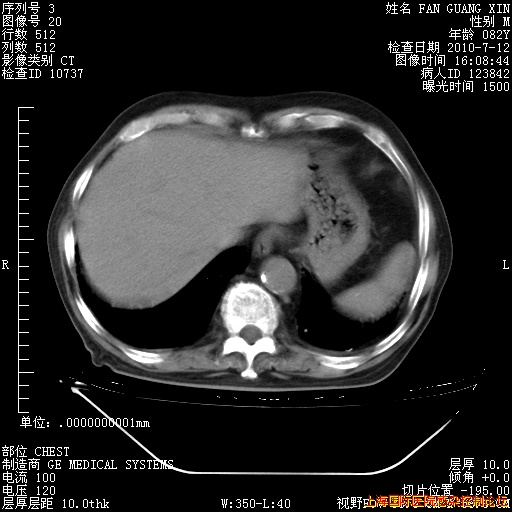

今天复查CT

回复

今天CT

整整相隔30天的肺部CT好像有所好转啊。甲强龙减量第3天,需要观察体温。